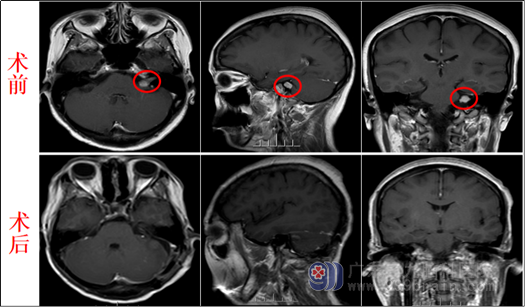

来自广东的陈阿姨半年前开始感到有头晕,同时左边耳朵听力相较于右边耳朵,有明显听力下降,于是去当地医院就诊,做了MR检查提示:患者左侧桥小脑角区有一个占位,为了进一步治疗,慕名来到了广东三九脑科医院。

入院后陈阿姨找到了欧阳辉教授,欧阳教授看了陈阿姨拍的MR片子解释道:陈阿姨左侧桥小脑角区有一个占位,考虑听神经鞘瘤可能性大,现在已经影响到陈阿姨的听力,手术指征明确,遂安排陈阿姨住院,完善相关检查,于9月18号在全麻全程电生理监测下行“左侧听神经鞘瘤切除术 ”。术中,医生先暴露桥小脑角池肿瘤,再小心磨开内听道后壁,在高清显微镜下细心保护好后组颅神经、三叉神经,精准解剖面、耳蜗神经,均予以完全保留,肿瘤全切除。手术很顺利,现陈阿姨恢复良好,完全没有面瘫。

影像检查: